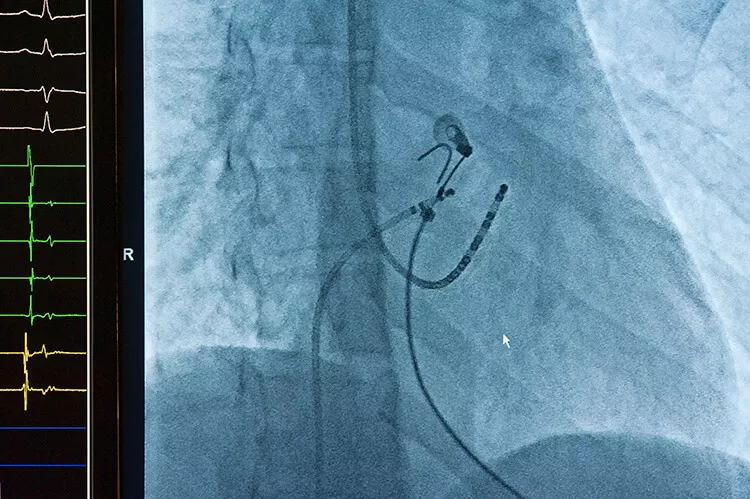

Doporučení Evropské kardiologické společnosti (ESC) u osob s fibrilací síní (FS), u nichž selhalo aspoň jedno antiarytmikum (ať již jde o FS paroxysmální či perzistující – nejsou-li přítomny zásadní faktory omezující šanci na udržení sinusového rytmu), již upřednostňují (I A) katetrizační ablaci (Hindricks G et al., Eur Heart J 2020) a u některých vybraných pacientů je možné ablaci provést i bez toho, aniž by předtím byla indikována antiarytmická léčba. Jde většinou o pacienty, kteří takovou léčbu netolerují – spadají sem sportovci nebo pacienti s bradykardií. Jde již o léčbu zavedenou, v současné době se u nás provádí relativně velké množství těchto výkonů a za rok 2020 jich český registr katetrizačních ablací KATAB eviduje cca 3 850. Jde přitom o nejčastější diagnózu, pro kterou se katetrizační ablace provádí, a velká pracoviště jsou schopna tyto výkony již provádět s minimálním rizikem komplikací.

Historicky spolu delší dobu soupeřily dvě ablační strategie, kdy jedna z nich využívala bodových ablací s kladením série termických lézí s cílem odizolovat plicní žíly (které u FS sehrávají hlavní roli) a druhá je zprostředkována katetry uzpůsobenými tak, aby plicní žílu izolovaly naráz (například s využitím kryobalonu zavedeného do plicnice). A do ablačního terénu již nastupuje i nová metoda, která je také postavena na elektrické aplikaci, avšak tentokrát stejnosměrného pole krátkých (v řádu mikrosekund až milisekund) a vysokoamplitudových pulzů, a která vede k vytváření pórů ve tkáni a poškození bifosfolipidové membrány, přičemž umožňuje selektivně ničit jen buňky myokardu, a nikoliv například ne až tak vzdáleně lokalizovaný frenický nerv nebo naopak jícen (Wittkampf FHM et al., J Am Coll Cardiol EP 2018).

Česká republika je v této terapii velice vpředu – jsme jednou z mála zemí, kde se tyto katetry již dají používat, a je dobře, že pacienti zde z této jednodušší, selektivnější, rychlejší, efektivnější a zdá se, že i bezpečnější metody mohou profitovat. Celý výkon se dá realizovat od vpichu do jeho ukončení za 40 minut. Je výhodou, že zákrok je možné provádět pouze pod rentgenem či intrakardiální echokardiografií a některé systémy jsou spojeny i s elektroanatomickým mapováním.